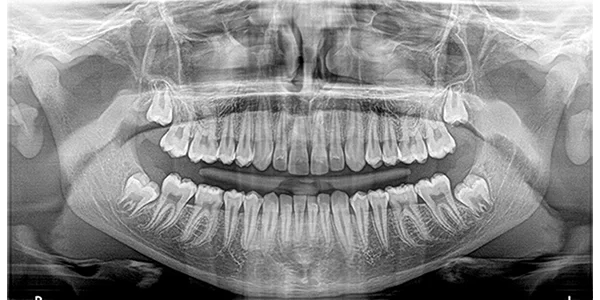

Cone Beam Computed Tomography (CBCT) is a unique type of X-Ray that allows a Dental Surgeon to see the Craniofacial structures, bone, soft tissues, and even nerve pathways of a patient, all in a 3D Image. Unlike Panoramic X-Rays which are 2 dimensional, the CBCT scan allows doctors to see buccal/Lingual distance, bone quality and surgically plan the placement of each implant.